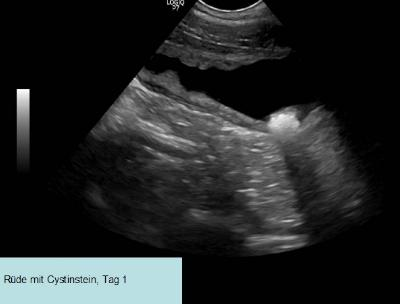

Hoewel statistische cijfers niet dramatisch lijken, is het verloop van de ziekte soms beangstigend. Als de urine verstopping niet snel wordt herkend en behandeld, kan de patiënt eraan overlijden. Daarom moet men onmiddellijk handelen als bij een urineonderzoek cystinekristallen worden aangetroffen! De snelle steen-ontwikkeling in drie dagen tijd is te volgen op de drie sonografische beelden van een aangetaste Ierse Terriër reu (Afbeelding 4a, 4b, 4c).

Foto’s van sonografische afbeeldingen van cystinesteenvorming in 3 dagen tijd, bron: eigen praktijkarchief.